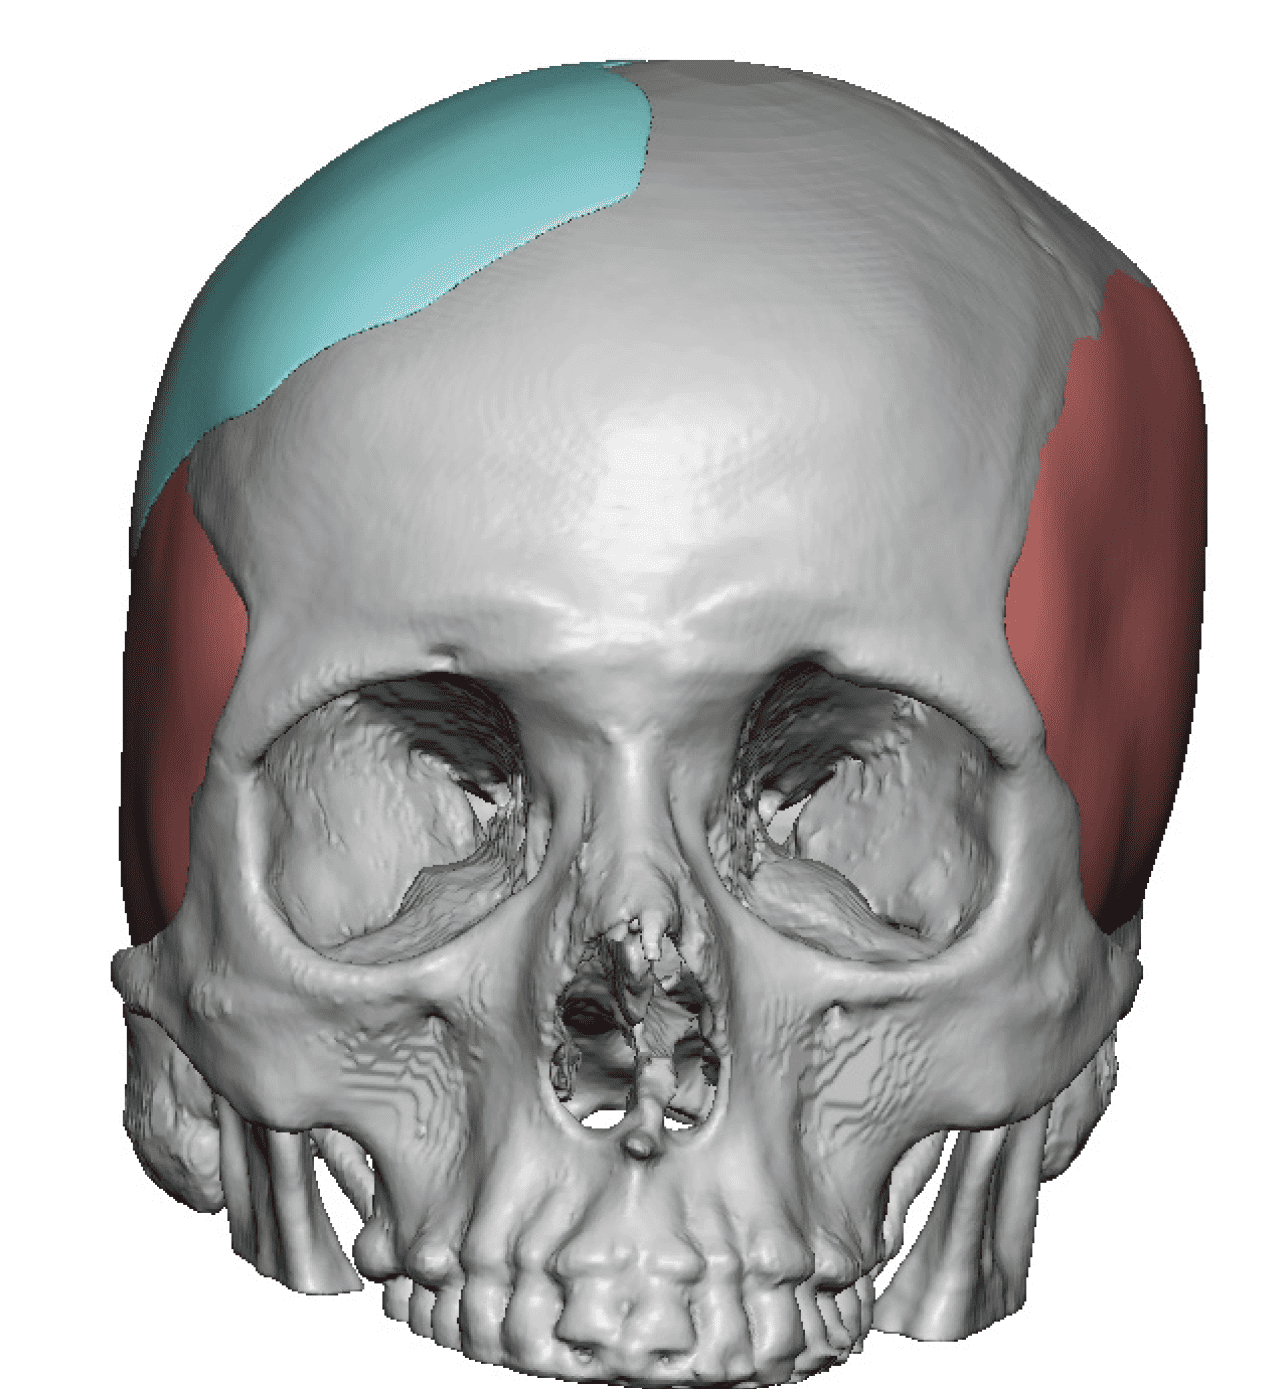

Patient 84

Desire for change of head shape from front view form an inverted V shape to a rounder and wider head shape.

Placement of custom extended forehead-temporal implants through incisions in the crease behind the ear. (he had a prior back of head skull implant which is green in the implant designs and which the head widening implants partially covered it)

Desire for change of head shape from front view form an inverted V shape to a rounder and wider head shape.

Placement of custom extended forehead-temporal implants through incisions in the crease behind the ear. (he had a prior back of head skull implant which is green in the implant designs and which the head widening implants partially covered it)